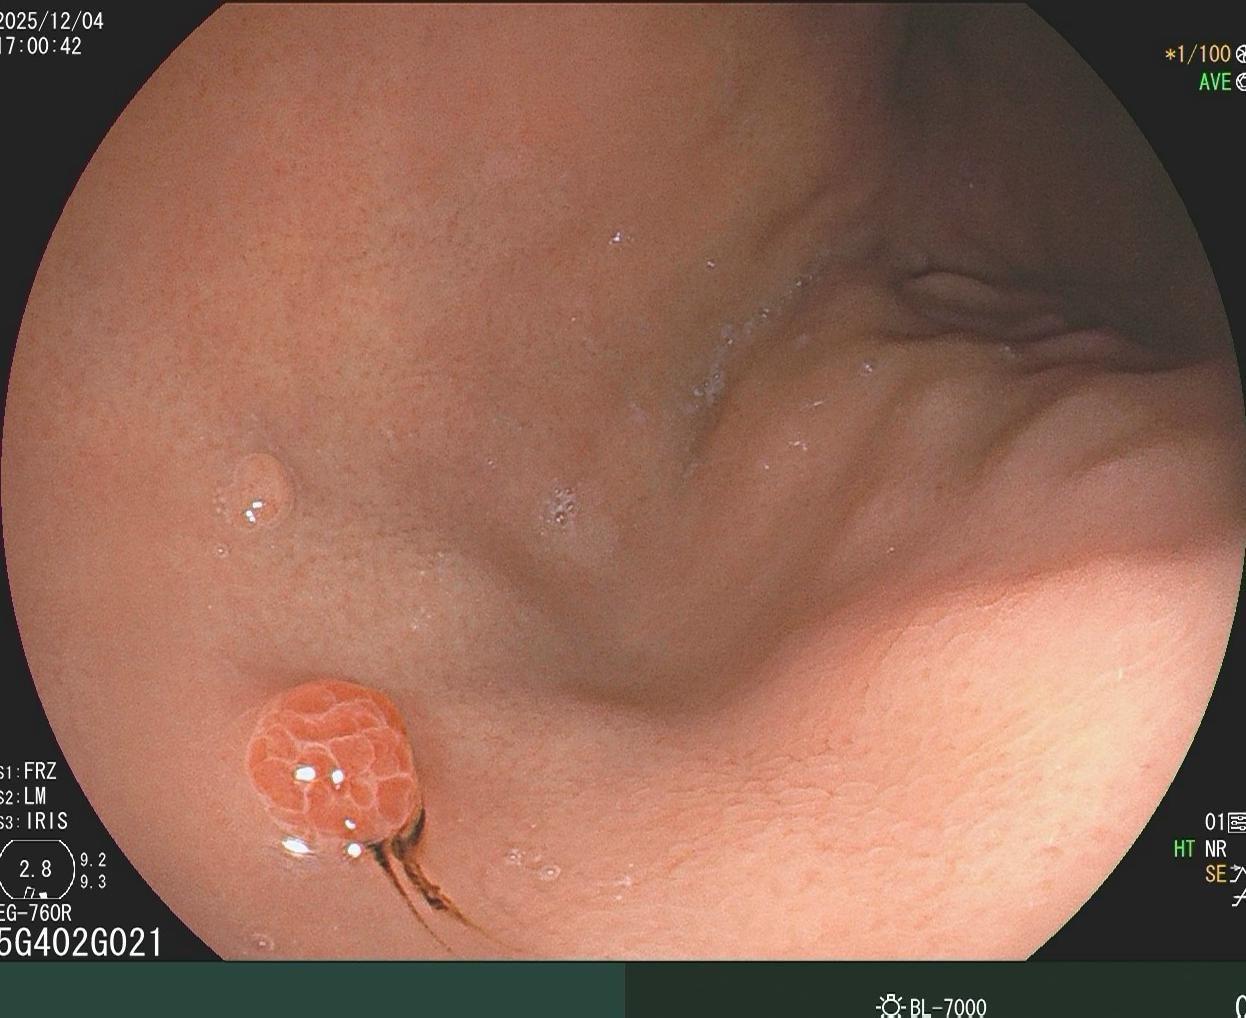

哇哦,树莓哎。小凹上皮肿瘤伴高级别上皮内瘤变,日常工作中并不常见,可惜...

2025-12-10 22:39